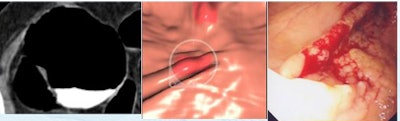

At histology, 22 of 34 (65%) had low-grade dysplasia, he said. No colorectal cancers were found. Two cigar-shaped true-positive lesions detected by CAD were dismissed by the radiologists due to low conspicuity.

![]() |

| Two true-positive lesions detected by CAD were dismissed by radiologists due to low conspicuity and a "cigarlike" appearance; both were also detected at conventional colonoscopy. |